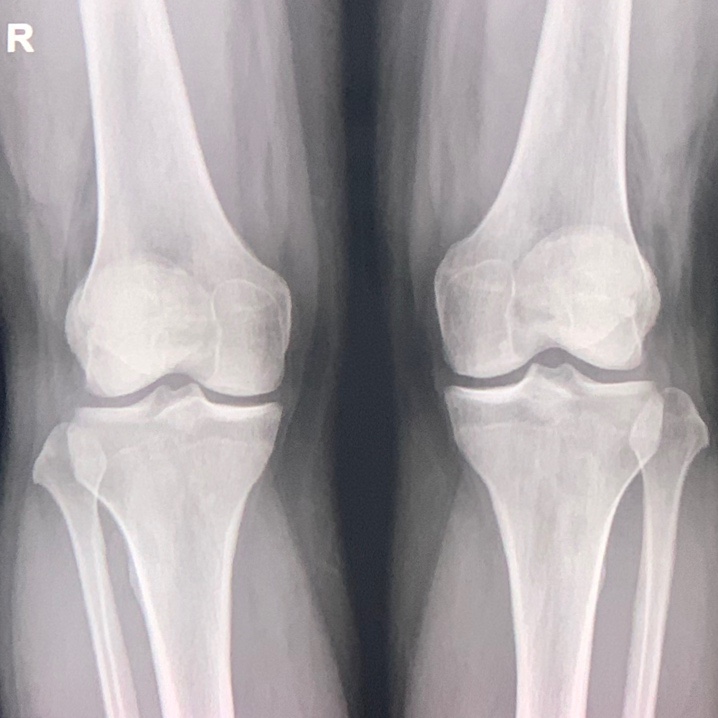

등산 후 무릎 통증으로 고생 중

슬개대퇴통증증후군 8월 18일, 무더운 여름 청계산 등산 하산은 1시간이면 충분하다는 말을 듣고 안 쉬고 ...